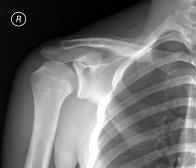

男,请根据其正常肩关节影像图像,判断其最可能的年龄 ( )A、36岁左右B、26岁左右C、46岁左右D、16岁左右E、56岁左右

问题 男,请根据其正常肩关节影像图像,判断其最可能的年龄 ( )

选项 A、36岁左右 B、26岁左右 C、46岁左右 D、16岁左右 E、56岁左右

答案 D